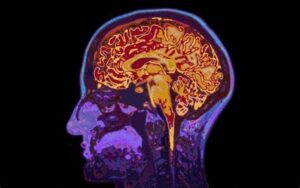

İki güçlü nörotransmitterin, dopamin ve serotoninin seviyeleri değiştirilebilir. İşte bu hormonlara nasıl müdahale edeceğinizin yöntemleri bu makalede sizi bekliyor.

Bu, Thomas Jefferson Üniversitesi ve Hastanesi'nden, bir haftalık ruhsal inzivaya katılan katılımcılar arasında beynin dopamin ve serotonin sistemlerinin değiştiğini gösteren araştırmadan gelen haberler.

Beyin taramaları da farklılıklar gösterdi. "Çalışmamız, yedi günlük geri çekilmeden sonra dopamin ve serotonin taşıyıcılarında önemli değişiklikler gösterdi, bu da katılımcıların bildirdikleri ruhsal deneyimler için birincil katılımcılara yardımcı olabilir." diye yazdı. Thomas Jefferson'da Bütünleştirici Sağlık ve “nöroteoloji” olarak bilinen bir alan olan dini ve manevi deneyimlerin nörolojisini inceleyen çalışmaları ile tanınır. Araştırmaları arasında Brezilya psişik medyumları, Sufi mistikleri, Budist meditasyoncular, Fransisken rahibeleri, Pentikostallar ve laik maneviyat ritüellerine katılanlar üzerine beyin tarama çalışmaları yer aldı.

Loyola meditasyon ve inziva grubundaki inziva sonrası taramalar, dopamin taşıyıcısında yüzde 5 ila 8 oranında azalma ve yüzde 6,5 oranında serotonin taşıyıcısında azalma olduğunu ortaya çıkardı, bu da nörotransmitterlerin daha fazlasını beyin için kullanılabilir hale getirebilir. Newberg, “Serotonin ve dopamin, beynin ödül ve duygusal sistemlerinin bir parçası olduğundan, bu uygulamaların neden güçlü, olumlu duygusal deneyimlerle sonuçlandığını anlamamıza yardımcı oluyor” diye yazdı.